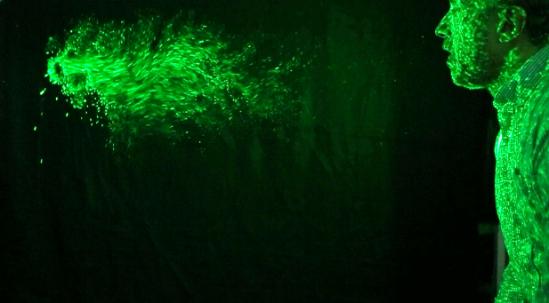

In April 2020, Professor Cahill therefore began investigating the problem of aerosol dispersion during surgery. Dr Nolan volunteered his time and expertise to this investigation, and his custom Schlieren facility was relocated to the old operating theatres of the Mater Hospital. Schlieren is a real-time optical technique, whereby local changes in the refractive index of air are made visible. In other words, by looking at how rays of light bend, this technique visualises human breath in the air in a striking way (see image below).

- Conducting a study, involving volunteers from hospital staff, to mitigate risks associated with high-flow nasal oxygen. This is often given to critical COVID-19 patients and generates a significant jet of gas from the airway, creating environments with high amounts of aerosol.